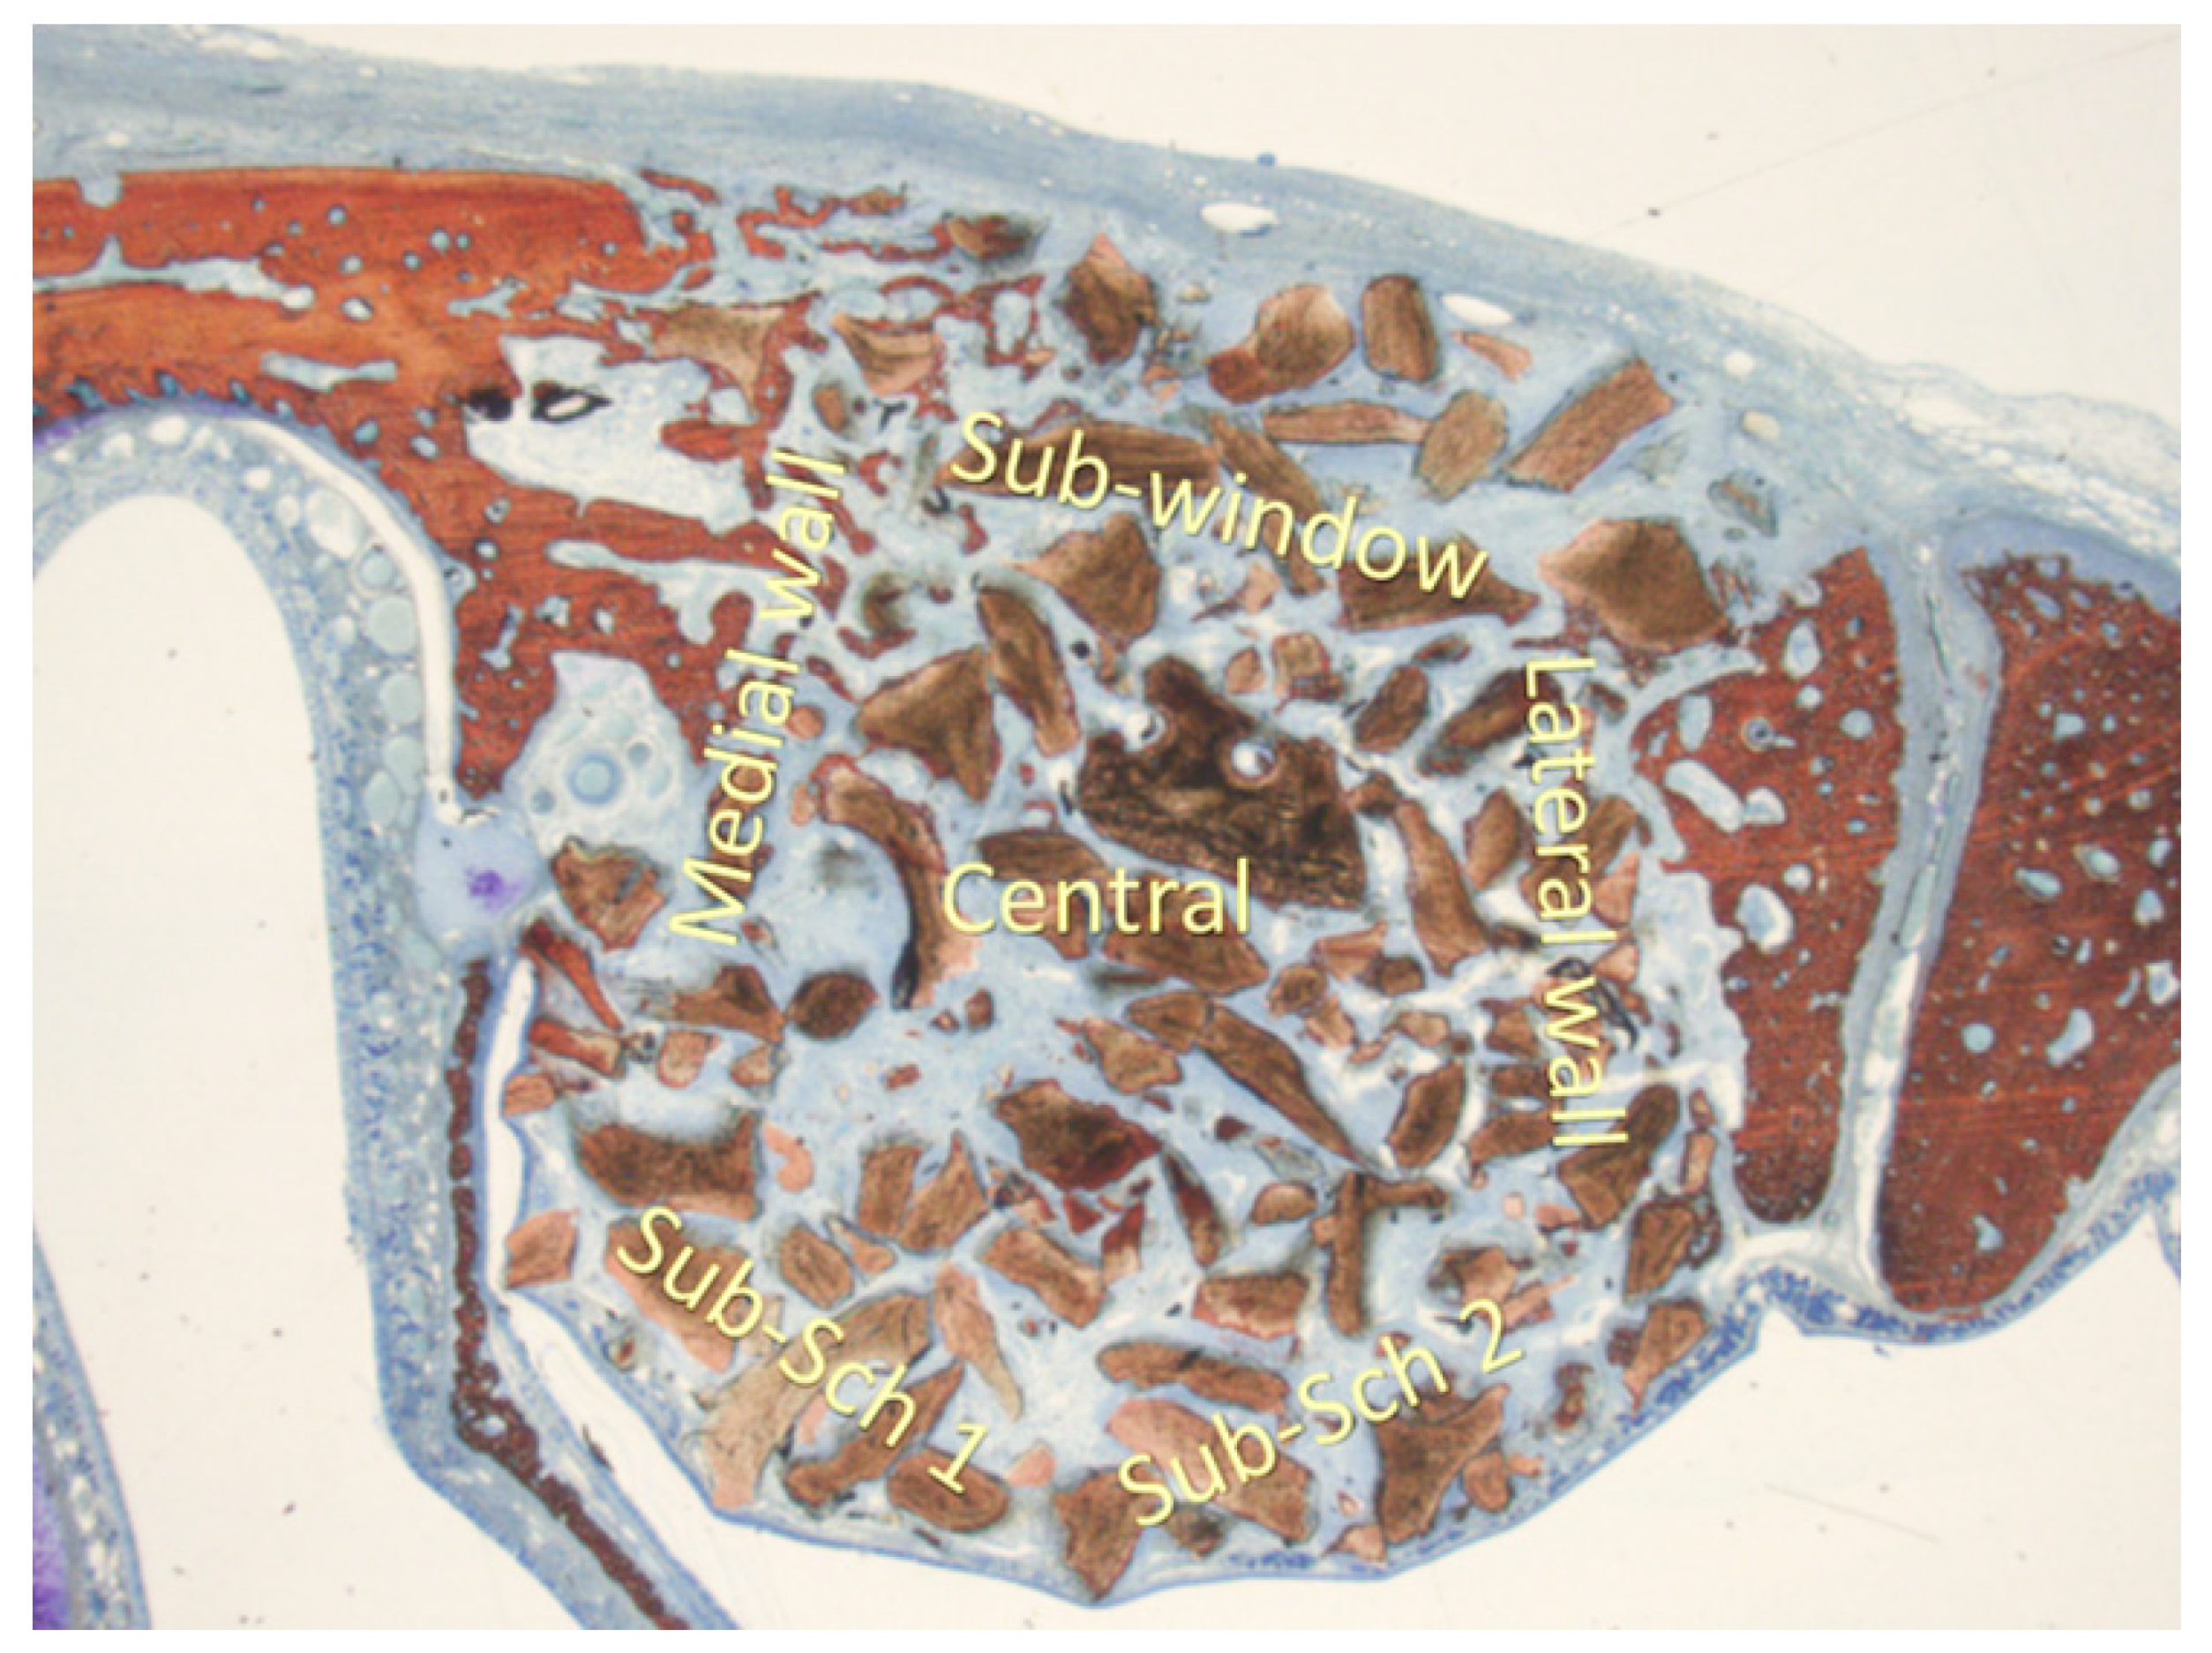

For morphometric evaluations, a 75 µm grid was applied to the images to quantify new bone formation, residual biomaterial, and soft tissue across five specific sinus regions: the sub-Schneiderian area (two grids), medial wall, lateral wall, central grafted zone, and sub-window area (Figure 2). These analyses were performed at ×100 magnification.

Figure 2.

The morphometric evaluation was performed in six areas: sub-Schneiderian (two areas), medial and lateral walls, central, and sub-window.